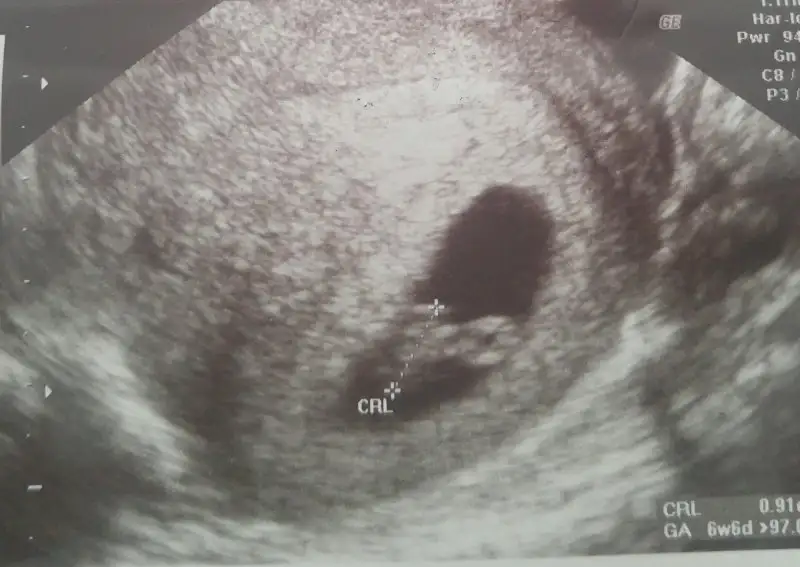

Benimde kizimda senin kiz gibiydi oglumdada simdiki ultrasyon resmin gibiydi. Sanirim bebosin oglan canim :)Eki Görüntüle 1895776 bu kızım 7 yıl önceki ultrason görüntüsü. Eki Görüntüle 1895777 buda şimdi ki

Senin oglum keseye göre tutmus buda kiz bence cünkü teori sende tutuyo :)Karından usg.ilk foto 6+3 ikinci foto 7 haftalık.